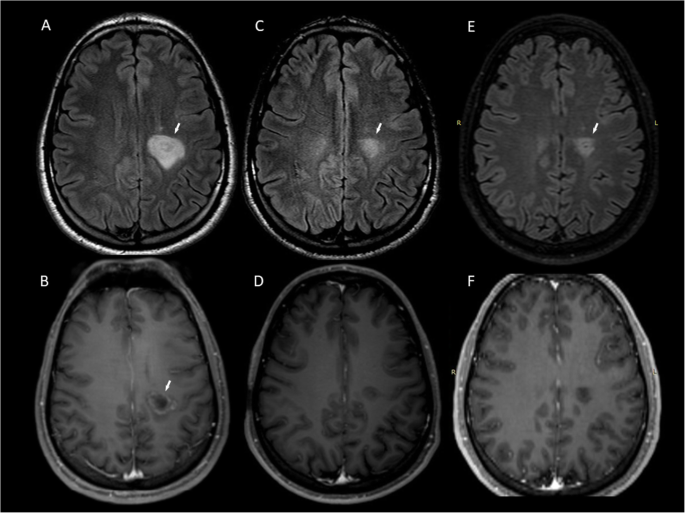

A 24-year-old man presented with right-sided hemiparesis and hemianaesthesia; a tumefactive lesion (2.8 × 2.5 × 2.5 cm) with “onion bulb” appearance on FLAIR images and partial contrast enhancement (Gd+) of the outermost layer (Fig. 1a-b) of the left corona radiata and 3 periventricular non-enhancing (Gd-) lesions were detected on MRI. CSF analysis showed OCB presence. Intravenous methylprednisolone (IVMP) was administered with poor clinical response and subsequently, he underwent seven plasmapheresis sessions (PLEX) with MRI activity deterioration. After 6 cyclophosphamide pulses (800 mg/m2/pulse) a remarkable clinical outcome was observed; follow-up MRI (15 months from symptom onset) showed residual ill-defined concentric morphology of the BCS-type lesion (1.7 × 1.4 × 1 cm) and no Gd + (Fig. 1c-d). A significant decrease in size of the BCS lesion and 3 new T2-weighted hyperintense small lesions were observed during a 5-year-follow-up MRI (Fig. 1e-f) and the patient was started on glatiramer acetate over the last year (Table 1).

MRI of Case 1 showing BCS-type lesion before and after treatment with cyclophosphamide. Tumefactive BCS-type lesion of the left corona radiata at symptom onset (A) with partial Gd + of the outermost layer (B arrow). A BCS-type lesion with residual ill-defined concentric morphology (C arrow) and no Gd + (D) 15 months from onset, after 6 pulses of cyclophosphamide. BCS-type lesion 5 years from onset (E arrow, F). a, c: FLAIR images. b, d: T1-weighted contrast-enhanced images. e: 3D FLAIR image. f: 3D T1-weighted contrast-enhanced image. BCS: Baló’s concentric sclerosis, Gd+: gadolinium enhancement